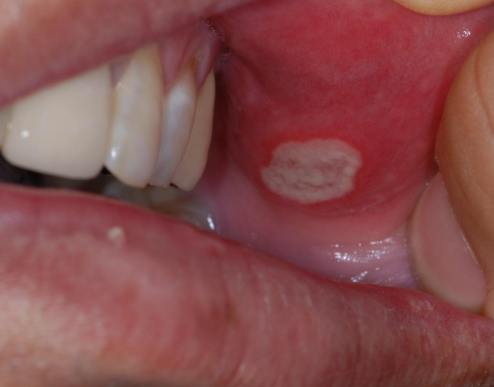

입술에 하얀 구멍이 생긴다거나 입안에 볼 쪽 피부, 혹은 혀, 잇몸 등 침이 닿는 부위에 존재하는 점막의 다양한 부위에서 구내염이 발생할 수 있습니다.

크게 궤양성 구내염, 미란성 구내염, 수포성 구내염 등이 존재하며, 혀나 혀 밑부분, 연구개, 입술선의 양쪽, 볼 안쪽 등 입안에서 움직이는 부분에서 주로 나타납니다.

구내염은 형태에 따라 궤양성 구내염, 수포성 구내염, 미란성 구내염 등으로 구분됩니다.

궤양성 구내염은 깊이가 얕고 크기도 작지만 여러 개가 모여서 발생하는 구내염입니다.

주로 입술 안쪽이나 뺨 점막, 혀의 가장자리에 1개~5개 정도가 옹기종기 모여있는 경우가 많습니다.